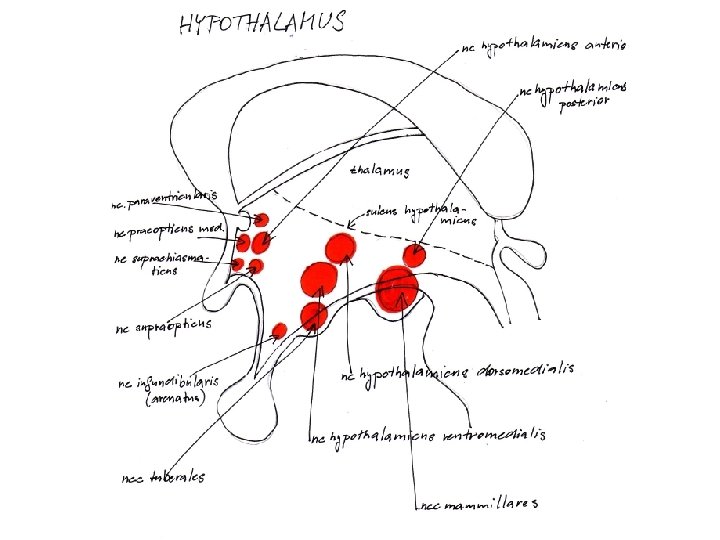

Hypothalamus • • je derivát visceromotorické zóny bazální ploténky nejvyšší autonomní ústředí infundibulum + hypophysis tuber cinereum (eminentia mediana) + corpus mammillare • area preoptica + chiasma et tractus opticus

Hypothalamus • infundibulum • tuber cinereum • corpora mammillaria • recessus infundibuli • recessus opticus

Hypothalamus – ohraničení • • nahoře: sulcus hypothalamicus dole: viditelný na dolní ploše mozku vpředu: lamina terminalis vzadu: přechází do tegmentum mesencephali • mediálně: 3. komora • laterálně: capsula interna

Hypothalamus 3 podélné zóny: periventrikulární, mediální, laterální zóna 3 příčné zóny: přední, střední, zadní hypothalamus Nuclei • přední hypothalamus (area hypothalamica rostralis) - nucleus paraventricularis, supraopticus, suprachiasmaticus • střední hypothalamus (area hypothalamica intermedia et dorsalis) nuclei tuberales laterales et ventromediales • zadní hypothalamus (area hypothalamica posterior) - nuclei mammillares, nucleus h. posterior, nucleus tberomammillaris

Hypothalamus – bílá hmota • fornix → corpus mammillare (nuclei corporis mammillaris) → tractus mammillaris princeps /rozdvojí se na/ → tractus mamillothalamicus → ncl. anteriores thalami → tractus mammillotegmentalis RF mozkového kmene (ncl. Guddeni) • stria terminalis corpus amygdaloideum → hypothalamus • stria medullaris thalami hypothalamus habenula

Hypothalamus – bílá hmota • fasciculus medialis telencephali = fasciculus prosencephalicus medialis = medial forebrain bundle (MFB) – mezi mediální a laterální zónou jader – propojují hypotalamus s korovým limbickým systémem + limbickým systémem mozkového kmene (+ RF) • pedunculus mammillaris - spojuje corpora mammillaria a nucleus dorsalis tegmenti Guddeni (v RF mesencephala) a fasciculus longitudinalis posterior Schützi ncl. v mediální zóně hypotalamu → autonomní jádra hlavových nervů (příp. až do míchy)